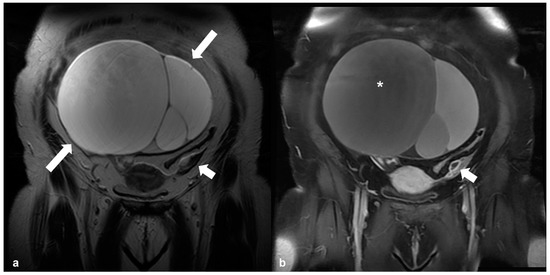

2.4.3. Dysgerminoma